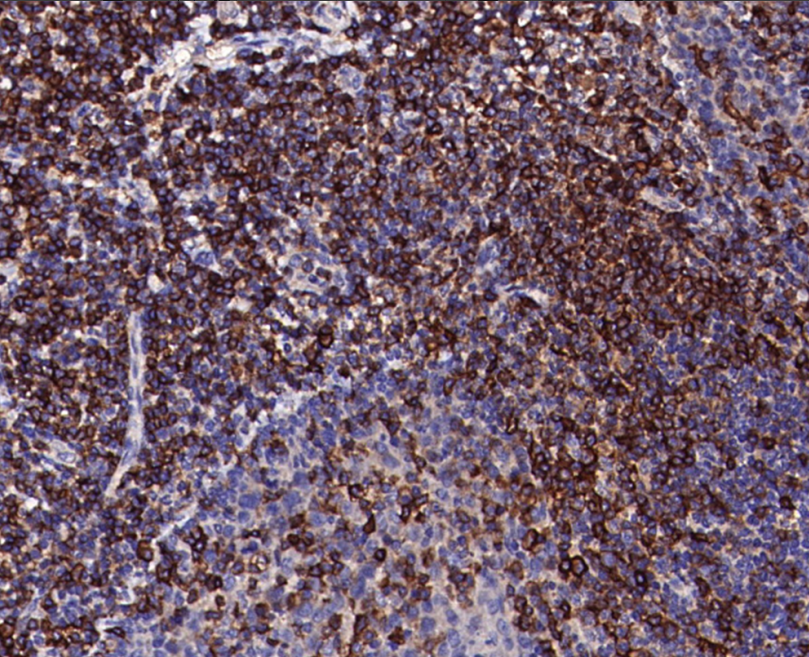

In some lymphohematopoietic tumors, the expression of CD27 is helpful in determining the origin of the tumor cells. In the differentiation between Hodgkin's lymphoma and non-Hodgkin's lymphoma, tumor cells of classical Hodgkin's lymphoma usually do not express CD27, while some types of non-Hodgkin's lymphoma, such as diffuse large B-cell lymphoma, may express CD27.In addition, in T-cell lymphomas, the expression of CD27 varies among different subtypes, which can help to further subdividing the tumor types and provide a basis for accurate diagnosis and treatment. The results will help to further classify tumor types and provide a basis for precise diagnosis and treatment.

CD27 Antibody Reagent binds specifically to the CD27 molecular antigen. Immunohistochemistry kits containing CD27 Antibody Reagent are suitable for the precise diagnosis of Hodgkin's lymphoma.